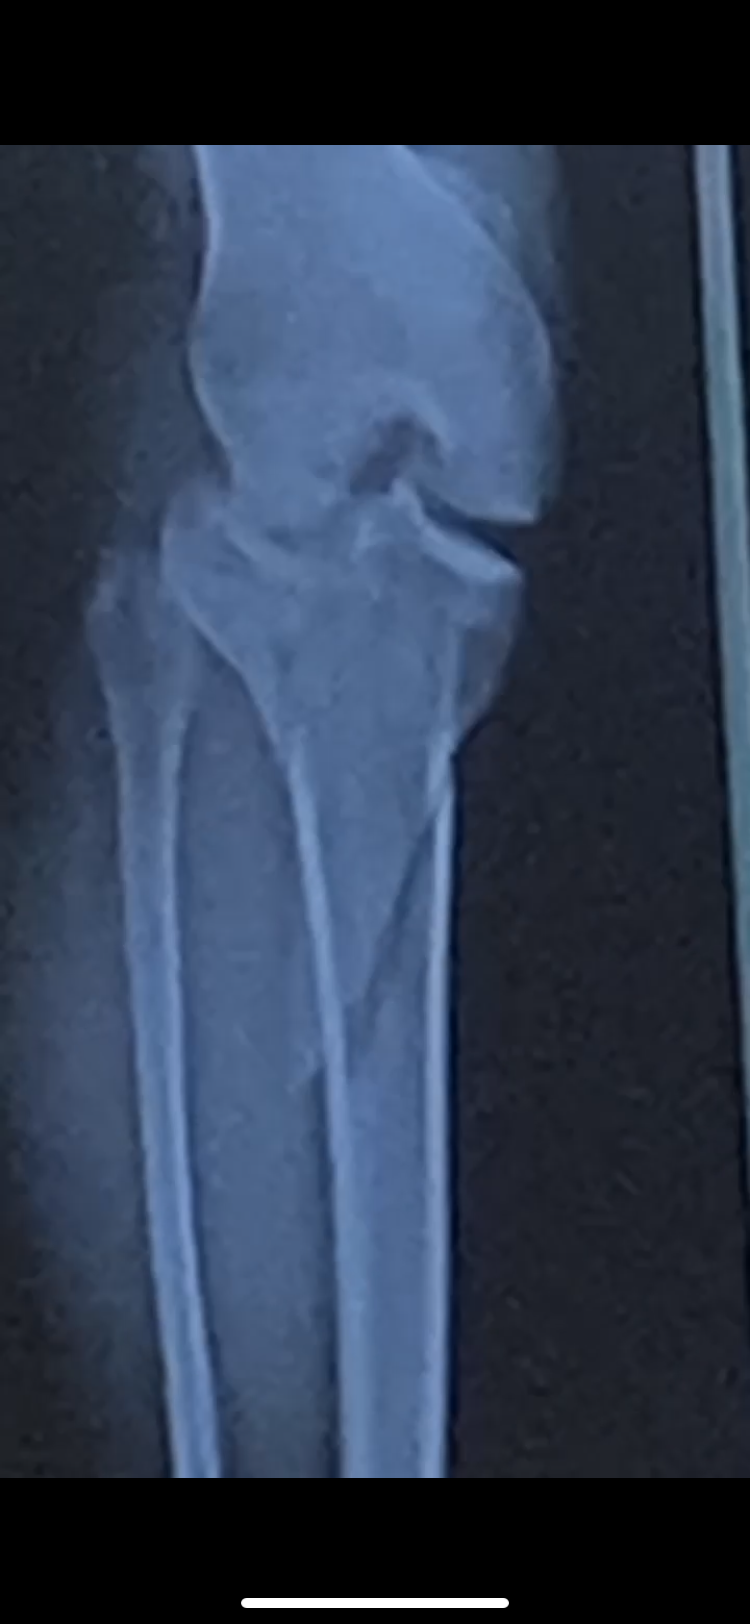

Hi everyone. My name is Kyler, I’m 22 years old and I recently fractured my tibia and had surgery to stabilize the bone. Unfortunately the healing process and physical therapy is a long road which means I’ll be out of work for at least three months with no income. I’m facing rent, groceries, and medical bills all on my own, and I’m really struggling to make ends meet.